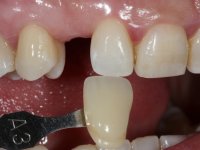

To define the dental zone to be covered by the Maryland bridge retainers, the patient was asked to perform maximum intercuspidation movements, and the contact points were marked with articular paper. Tooth preparation of the interproximal surfaces was made, to create a prosthetic insertion axis. It was sought that the mesio-distal diameter at the incisal level was equal to the diameter mesio-distal at the cervical level, that is to say, the interproximal walls were parallelized. Tooth preparation was done with fine grain diamond drills, and later polishing was done with abrasive discs. Color information was collected even before confection of the impression, to avoid dehydration of the arcade. Definitive impression was made using wash technique impression with silicone of heavy and regular consistency, both with fast setting, and a working plaster model was prepared in the lab. A laboratory scanner was used to scan the working model, and later, the infrastructure for the Maryland bridge was made using a CAD-CAM process. Ceramic was placed on this subframe. A ceramic adhesive was applied to the internal surface of the wings and connectors, which would enable bonding to the adjacent teeth. The adhesive bridge was bonded in the mouth following the conventional bonding technique. After bonding, the protrusion and laterality movements were carefully checked to avoid undesirable contacts.